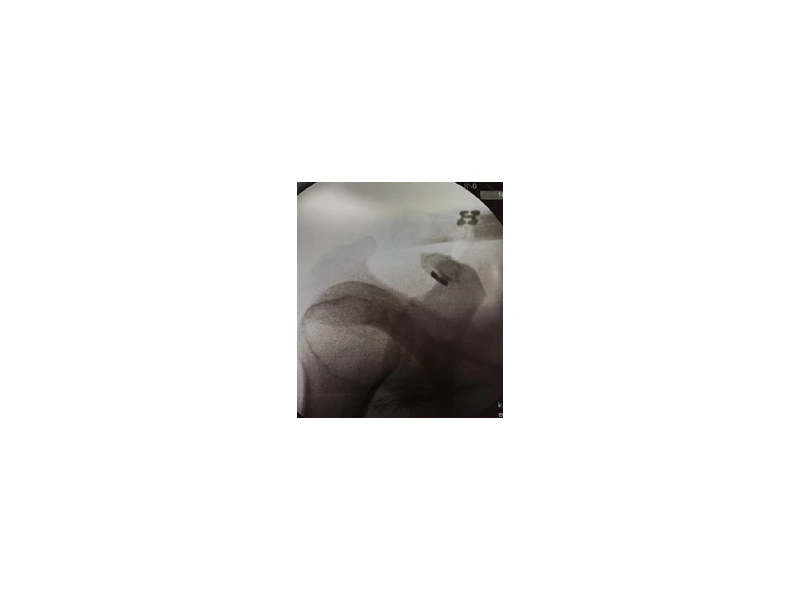

Η χειρουργική θεραπεία έχει άριστα αποτελέσματα, ιδίως στις πρόσφατες βλάβες, δηλαδή μέχρι και 2 εβδομάδες μετά τον τραυματισμό. Η επέμβαση γίνεται υπό γενική αναισθησία , αρθροσκοπικά ή και mini open τεχνική, όπου ανατάσσεται και συγκρατείται η κλείδα με δύο κουμπία τιτανιού και ισχυρό ράμμα. Ο ασθενής μπορεί να αποχωρήσει από το νοσοκομείο λίγες ώρες μετά το χειρουργείο, φέρει φάκελλο ανάρτησης ώμου και λαμβάνει ήπια αναλγητικά χάπια για περίπου 5 ημέρες.